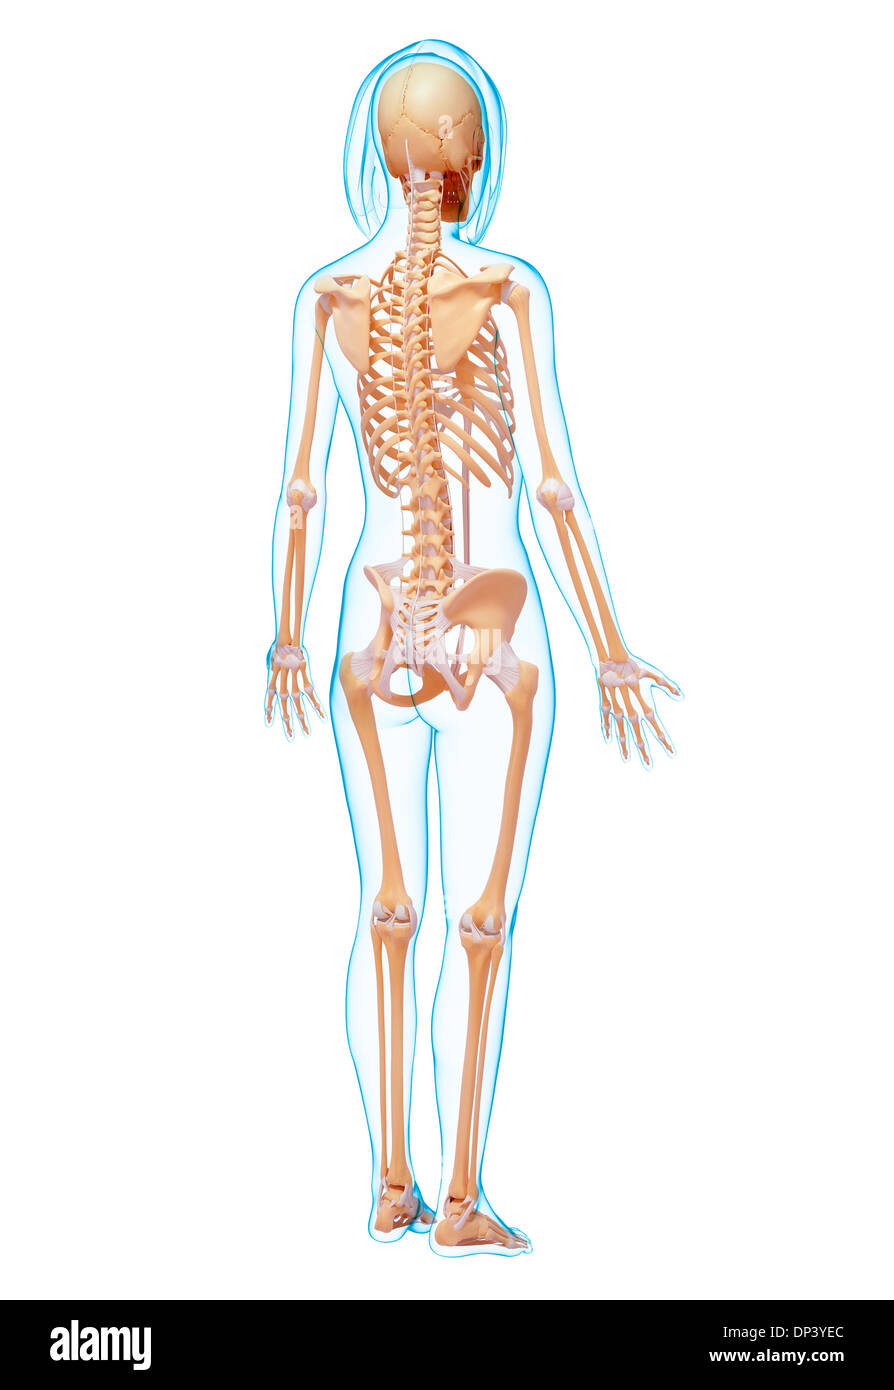

, Artwork Banque D'Imageshttps://www.alamyimages.fr/image-license-details/?v=1https://www.alamyimages.fr/artwork-image65240964.html

, Artwork Banque D'Imageshttps://www.alamyimages.fr/image-license-details/?v=1https://www.alamyimages.fr/artwork-image65240964.htmlRFDP3YEC–, Artwork